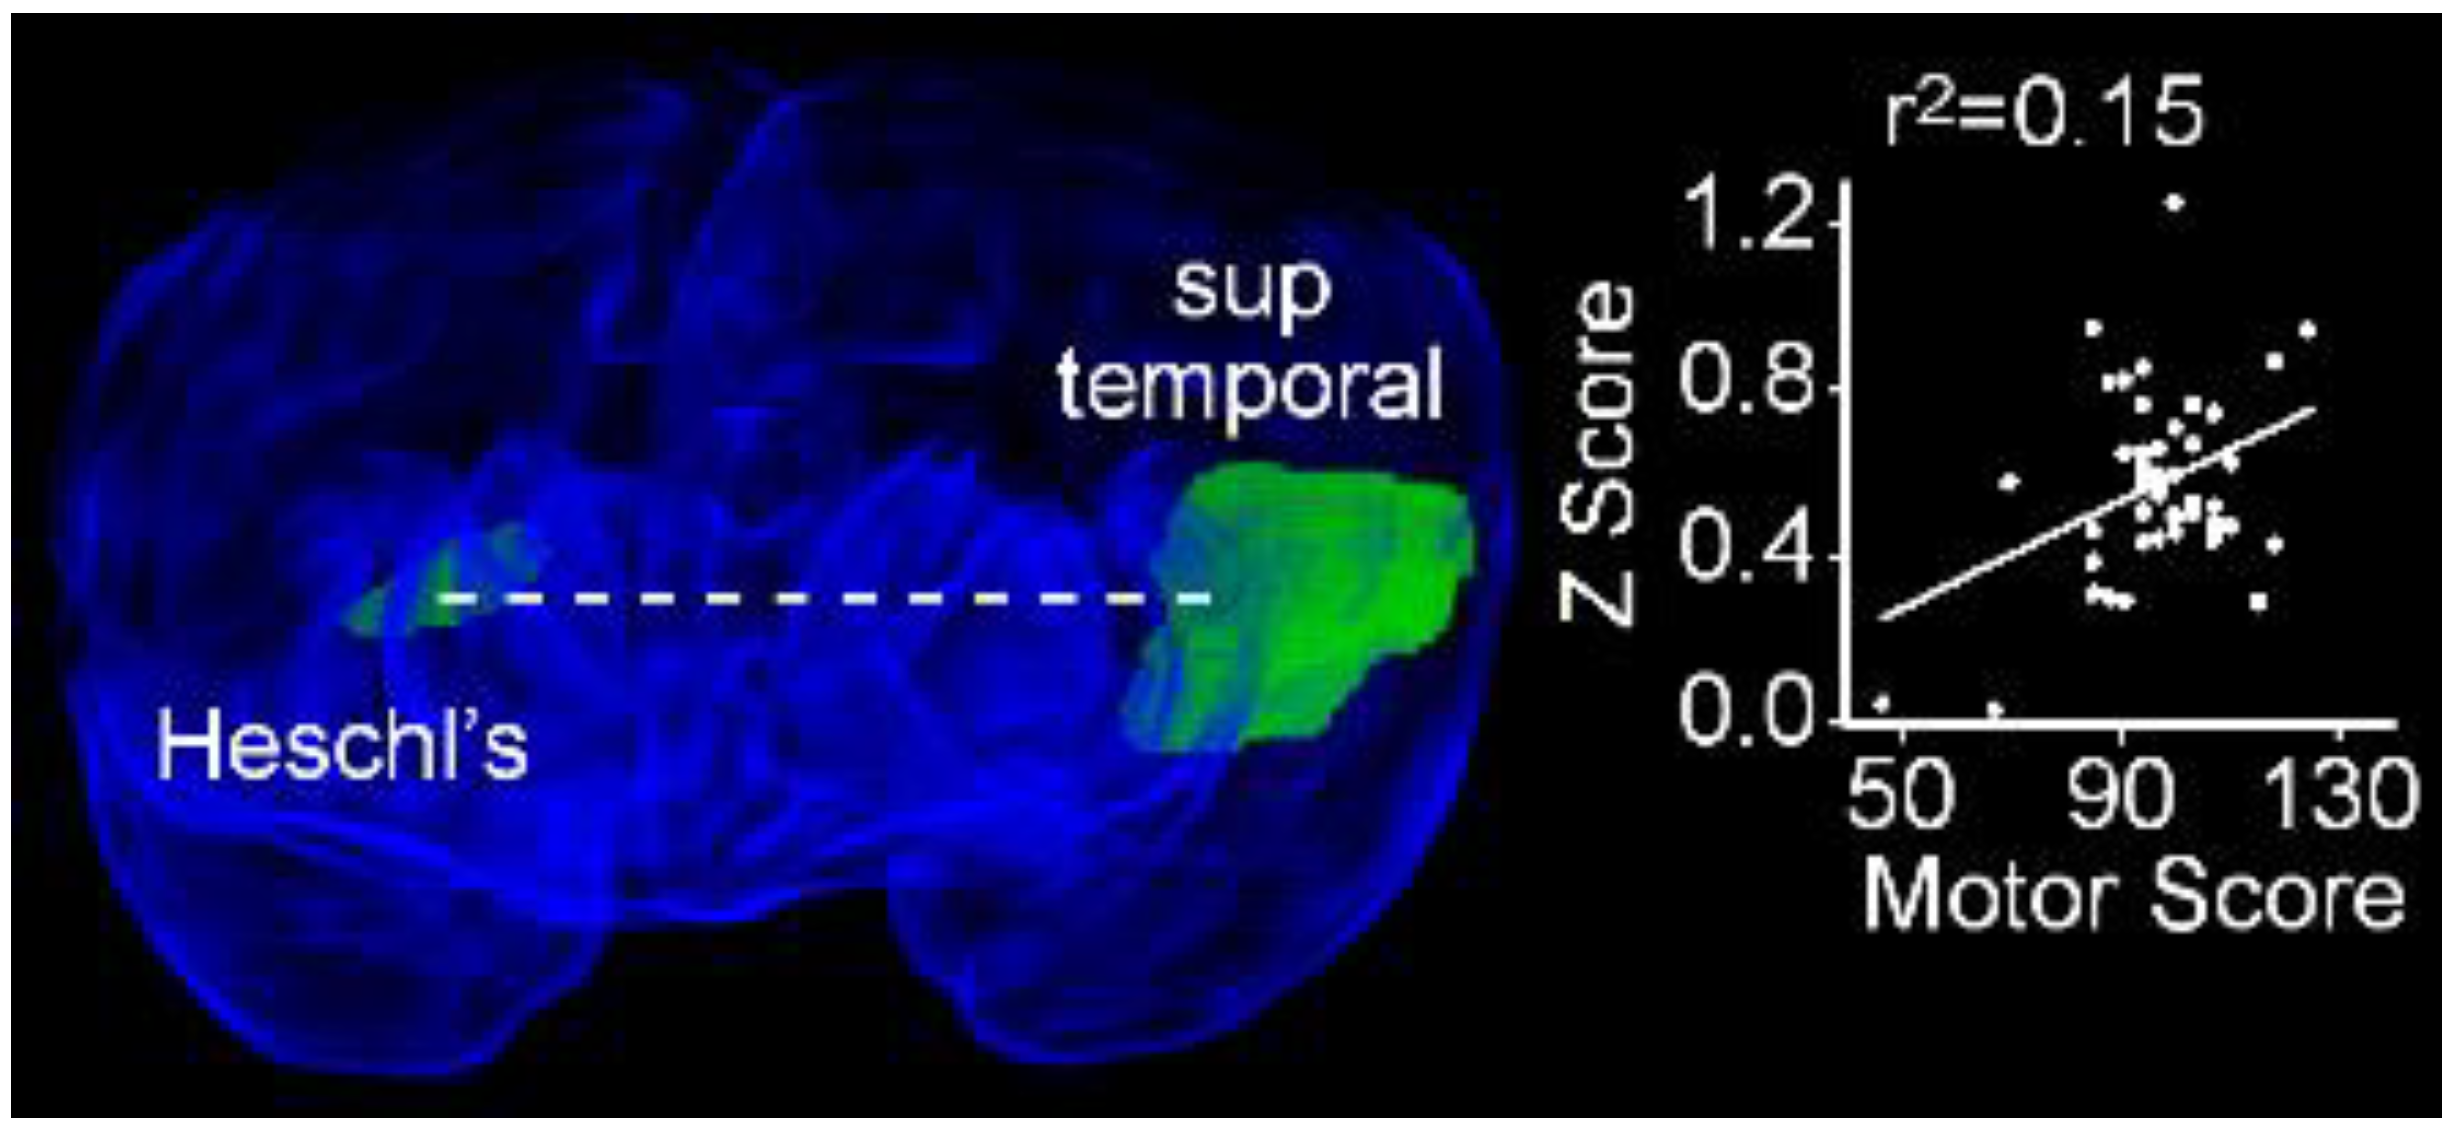

Having identified rsFC differences between normal and adverse long-term neurodevelopmental outcomes, we searched for brain regions between which functional connectivity at term demonstrated a significant linear relationship as a function of performance at two years on subscales of the Bayley III. We identified a single region pair in which rsFC increased as a function of performance on the motor subscale: the left superior temporal gyrus and the contralateral Heschl’s gyrus (r2 = 0.15; PFDR = 0.016, Figure 9).

Figure 9. Resting state functional connectivity between the left superior temporal gyrus and contralateral Heschl’s gyrus exhibits a positive linear relationship with performance on the motor subscale of the Bayley III. Obliquely projected 3D reconstruction of MRI images of cerebral grey matter and identified parcellated regions derived from a neonatal atlas. Dashed white line depicts the connectivity relationship. Inset: Individual Fisher-transformed Z-scores of correlation coefficients between regions.